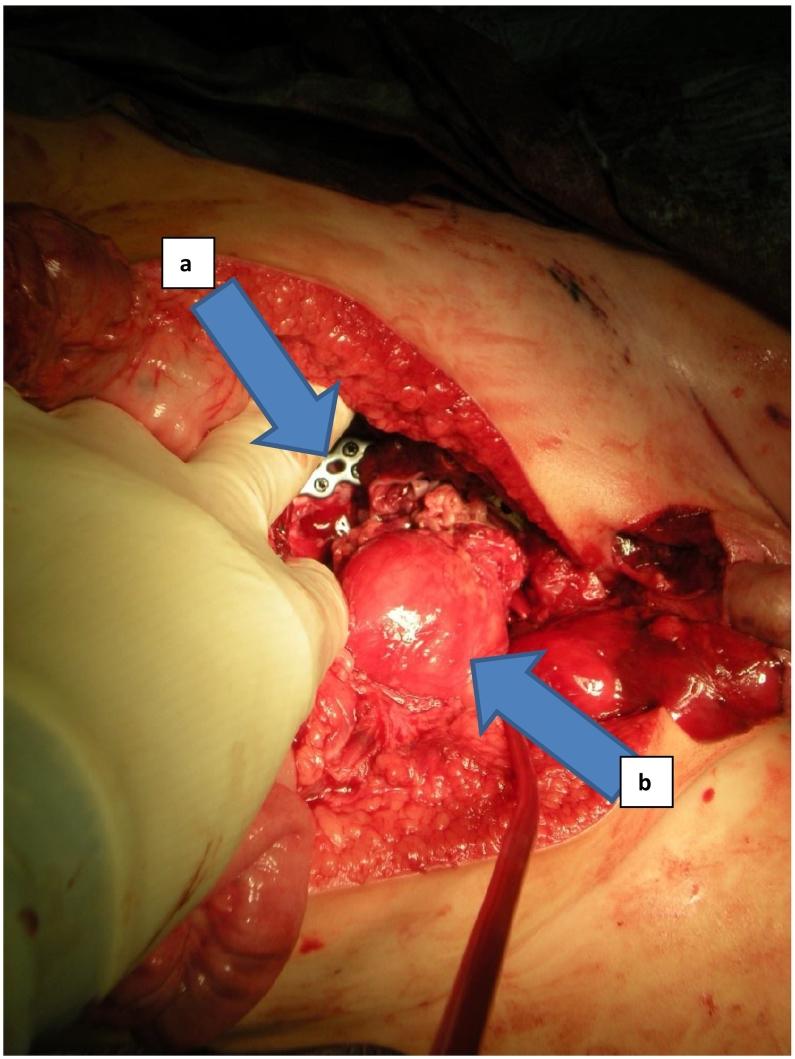

We report on a 14 months old toddler who sustained a traumatic hemipelvectomy by being crushed between a car and a stone wall. After stabilization in the resuscitation room he was treated operatively by laparotomy, osteosynthesis of the pelvic ring, reconstruction of the both external iliac vessels and the urethra and reposition of the testicles. After 66 days he was discharged into rehabilitation. Implants were removed after eight months. 20 months after the injury, the leg was plegic, initial radiological signs of femoral head necrosis showed up but the infant was able to walk with an orthesis and a walker. Up to our knowledge, this is the youngest patient described in the literature with a survived traumatic hemipelvectomy and salvaged limb.